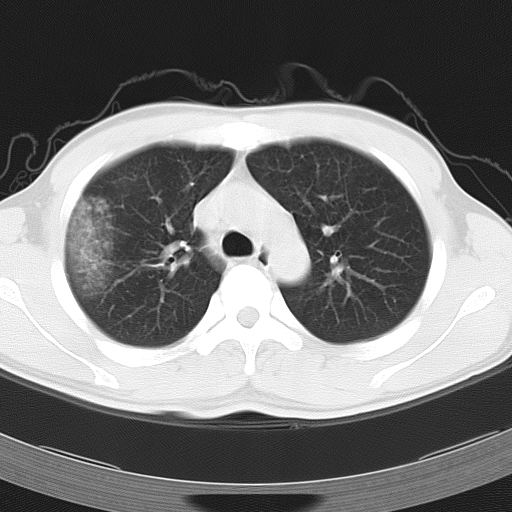

标题: CT12379:男,34岁,肺部病变,请求会诊!

男,34岁,咳嗽2~3个月,无咳血,病初有发热。

ct表现 (1)中央型:表现为蝶翼状浸润性阴影对称分布于两侧肺门周围,其内可见支气管充气征,病变区与正常肺组织分界清楚。(2)外围型:表现为多发性条片状、斑片状及斑块状高密度影,弥散、对称或不对称分布于两肺或一侧肺外围部位。病变区与正常肺组织及脏层胸膜面分界清晰,呈地图样改变。hrct可显示小叶间隔增厚及肺小叶内淡淡的密度增高影等细微结构,同时易发现肺大疱、肺气囊及节段性肺不张。

再仔细阅读该病人的ct片,我们不难发现,病例所表现的正是外围型的肺泡蛋白沉积症表现,即:为多发性条片状、斑片状及斑块状高密度影,弥散、对称或不对称分布于两肺或一侧肺外围部位。病变区与正常肺组织及脏层胸膜面分界清晰,呈地图样改变。

该病人经过1周抗炎治疗,病灶基本消退,仅存毛玻璃样改变。

但根据文献记载(http://baike.baidu.com/view/778576.htm),肺泡蛋白沉积症 无特殊治疗﹐60~70%的成人患者可自行恢复。故本人还是觉得该病例自愈的可能性比较大,跟抗炎治疗无直接的关系。